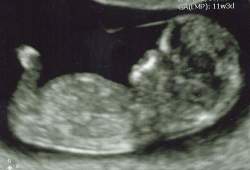

I was supposed to go but I had really bad cramps and saw a trace of blood, I call to see if it was just gas.they ended up doing a nuchal scan a week earlier than planned and everything is fine, but my last few urine tests had traces of blood, and my doctor thinks that's just a normal thing for me, and to drink more water.

DH calls this the alien and the backwards seahorse. (i only have one in there but the two pictures look different).